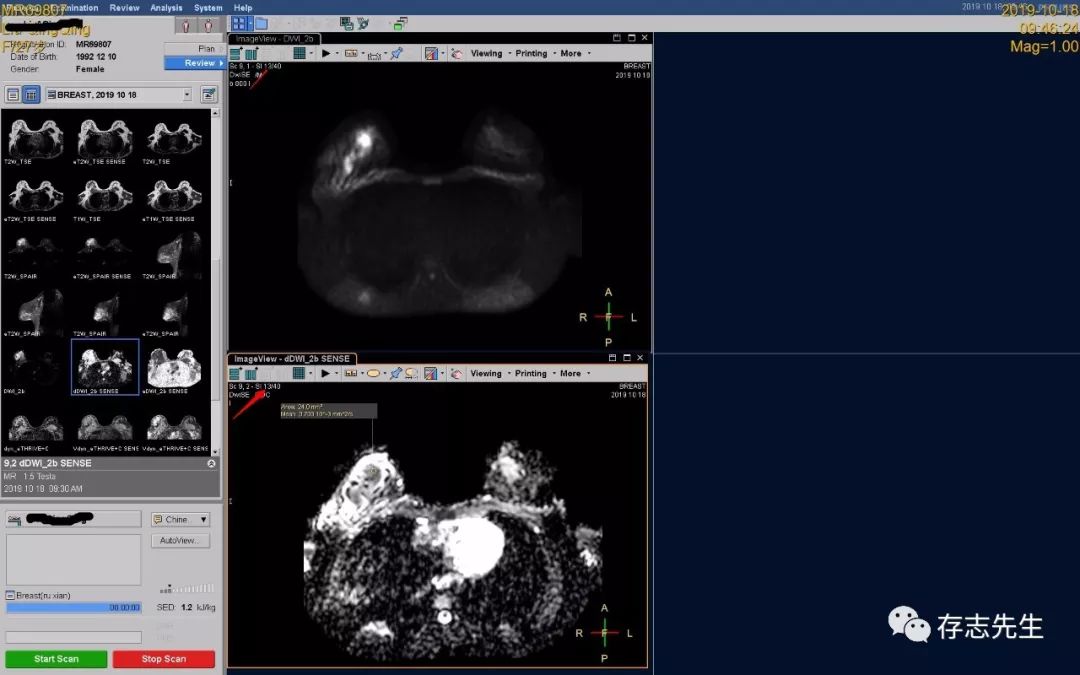

1、ADC值的测量:根据DWI受限位置对感兴趣区域做ADC值,用于辅助诊断。很多人找不到ADC图上病灶的位置,请记住弥散受限的层数,到ADC图上找到相应的层数,找病灶的位置,测得时候尽量画好感兴趣区域,以免带来不必要的误差;

然后保存上传即完成了ADC值的测量。